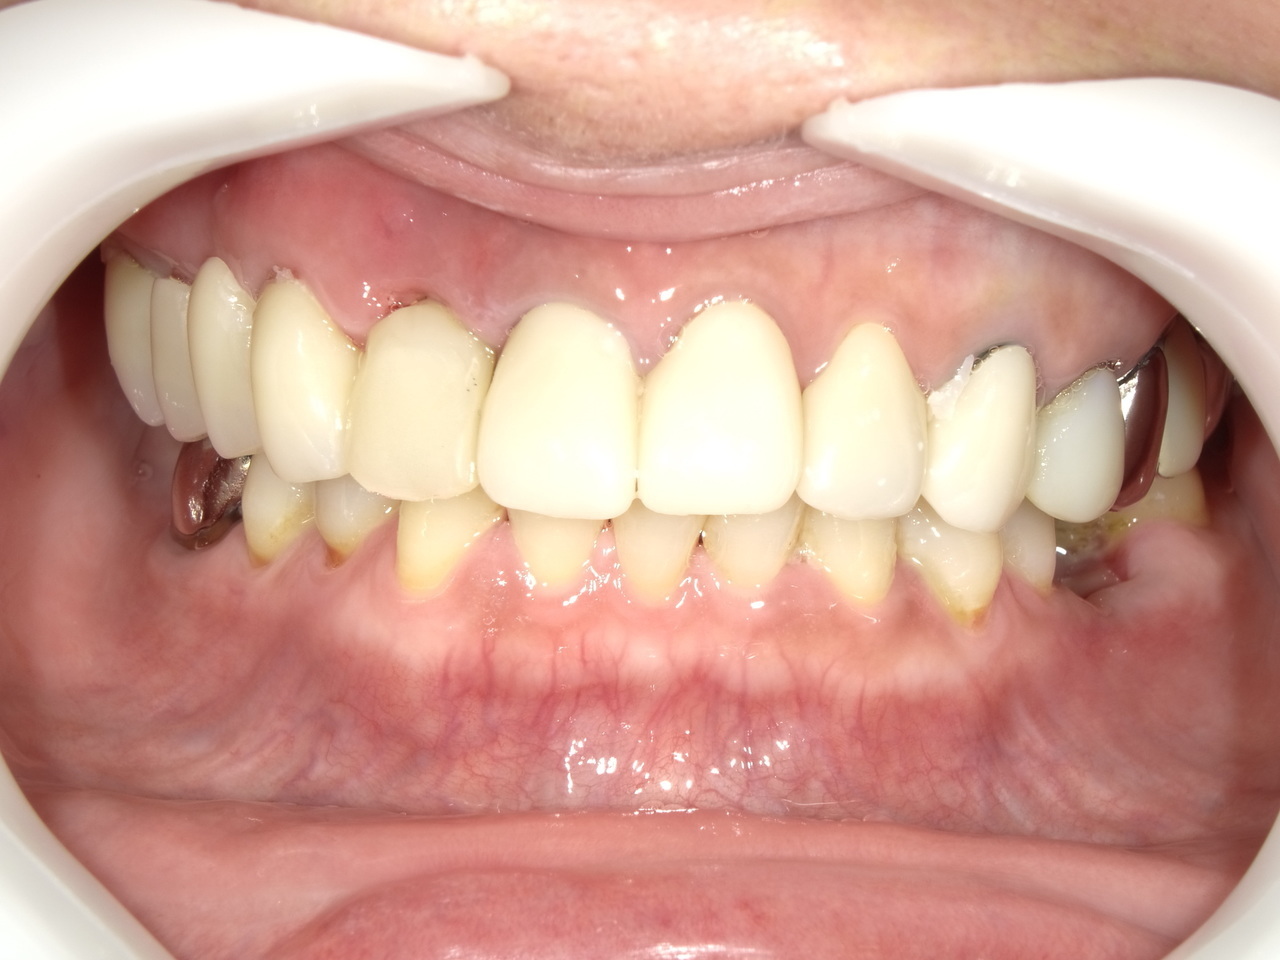

5.左上4番のインプラント抜歯即時埋入、左上6番の上顎既存骨1から2mmのグラフトレスサイナスリフト、左下56の大幅な骨欠損により、下顎神経の損傷を回避するために、ショートインプラントを使用し、左下56にインプラントを埋入し、最終補綴物は、左上456の3ユニットのジルコニアブリッジし、左下56は、ジルコニアの連結冠を装着したケース

After

枚方市のインプラントの症例

M・I 様 女性 70代

症状としては、左下56は、歯周病で欠損したと考えられるが、かなりの骨欠損をともなっていた。左上456に関しては、動揺が大きく、炎症が起き、排膿、および、歯性上顎洞炎を起こしていた。

治療法としては、動揺がひどくなってきて、炎症の症状もあったため、左上56の抜歯を希望。インプラント治療をその後、希望したため、左上4に関しては抜歯即時埋入。左上6に関しては、既存骨1から2mmでインプラント治療が厳しい状態であったが、グラフトレスサイナスリフトを行い、治療期間5か月はかかるということを説明して、インプラント埋入をおこないました。その後、2か月半後、大幅に骨が欠損している下顎56に対して、ショートインプラントを使用して、下顎神経の損傷を避けて、インプラント埋入を終えています。その後2か月後に光学印象で印象を行い、上顎刺億456歯、3ユニットのジルコニアブリッジを装着。下顎左側56に関しては、骨欠損が大きいため、歯冠長がだいぶ長くなるため、ジルコニアの連結冠を装着して治療を終えた。

治療結果は、上顎6に関しては、既存骨が少なく、厳しい治療ではありましたが、5か月で治療を終え、患者様の負担を最小限に抑えるができたと考えます。(従来のサイナスリフトでは、このようなケースでは1年以上、1年程度の治療期間がかかるか、治療が不可能と言われるケースだと考えます。)また、下顎は骨欠損が大きく、下歯槽管のリスクが起きることが考えられますが、ショートインプラントを使用することで安全に治療を行うことができました。

治療の期間・回数:治療期間5か月(上顎456 3ピースブリッジの治療は5か月(上顎既存骨が2mm程度しかなく、骨結合に時間がかかるケースであったために、5か月の治療期間が必要であった。)(左下56に関しては2か月半で治療を終えています。)治療回数は、13回。

治療の価格:1,474,000円(税込)

治療費の内訳:左上46および左下56のインプラント基本料(フィックスチャー及び手術費用、投薬費用、レントゲン費用、インプラント上部費用(アバットメントおよびジルコニアクラウンの費用用)330000円(税込み)×4本分 1320000円(税込)。左上5ジルコニアポンテック費用88000円(税込)。オプション費用、左上4抜歯即時埋入加算(人工骨費用を含む)+グラフトレスサイナスリフト費用 33000円(税込)、左上6グラフトレスサイナスリフト費用 33000円(税込)

治療のリスクや副作用:手術後に、痛みや腫れ、出血、合併症などを引き起こす可能性があります。噛む感覚がご自身の歯と異なる場合があります。見た目がご自身の歯と異なる場合があります。手術後にメインテナンスを継続しないと、インプラントが抜け落ちる可能性があります。